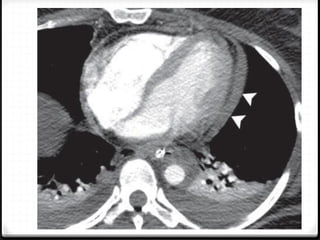

0 Pneumomediastinum

0 Pneumocardium

0 Hemopericardium

Pneumomediastinum

0 Cedera pada jalan nafas

0 Tingkat kematian tinggi

0 Jarang, 0.2%–8% dari seluruh kasus trauma thoraks

Pneumothoraks + pneumomedistinum + emfisema subkutis

hidropneumo

pericardium